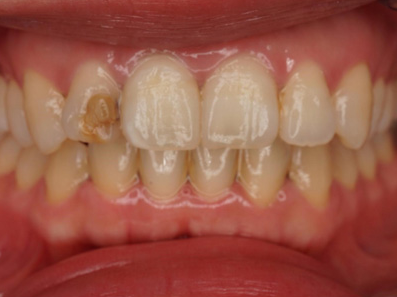

before

after

CASE 01

前歯の虫歯の治療

• 施術概要

虫歯の部分だけを最小限丁寧に取り除き、周りの歯の色になじむ自然な白い素材(レジン)で、元のきれいな形に整えます。これにより、口元の見た目をより自然な印象に近づけることを目指します。ダイレクトボンディングを実施。

• 金額

33,000円(税込)

• 期間・回数

小さい虫歯に関しては1回。 虫歯が神経まで到達している場合は、治療回数は2〜4回かかります。

• リスク・副作用

経年劣化によりレジンがすり減ったり着色し、将来的に再治療が必要となる場合があります。